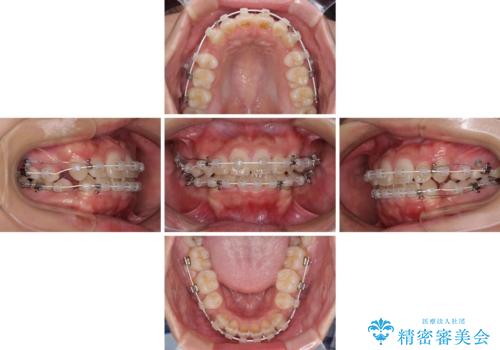

気になる八重歯を治したい 目立たないワイヤーでの抜歯矯正

- 前歯のデコボコと口元の突出感を気にして来院された患者様です。

上下左右第一小臼歯4本を抜歯し、ワイヤー装置にて口元を引っ込めるよう矯正治療を行うこととしました。

非常にスムーズに歯列移動が行われ、当初は2-2.5年を予想していましたが、僅か1年4ヶ月で治療を終えることができました。